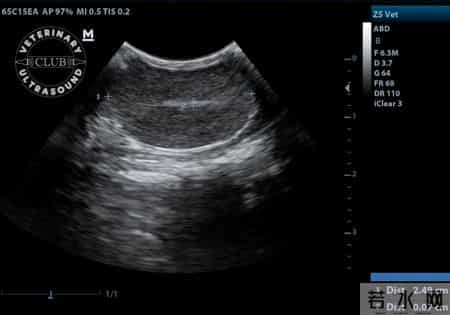

门诊中,一位60多岁的男性患者这样问。他的手里攥着一份前列腺B超报告,神情有些紧张。报告显示“前列腺体积增大,残余尿增加”,但是没有明确写明“问题严重”或“需立刻治疗”。他有点迷茫,也有点不安。

这两个指标,一个叫前列腺体积,一个叫残余尿量。

前列腺体积的增加,意味着尿道受到压迫,排尿阻力增大。残余尿量升高,则说明膀胱未能排空,尿液残留。这种长时间残尿的状态,容易引发感染、结石,甚至反复损伤肾功能。

临床上,有些患者的B超结果显示:前列腺体积超过35毫升,残余尿超过100毫升。

这类情况虽然不代表必须立刻手术,但医生通常会建议密切观察,必要时干预,因为这可能是“进行性增生”的预兆。根据临床经验,体积超过40毫升的患者中,有一部分在1-2年内出现排尿困难加重、夜尿增多、甚至急性尿潴留的情况。

目前临床参考值为:前列腺体积小于30毫升,残余尿小于50毫升为较理想状态。但这并非“绝对界限”。个体差异显著,有的人体积稍大但无症状,有的人即使体积不大,却排尿困难严重。医生判断时会结合症状评分、尿流速、夜尿次数等综合评估。